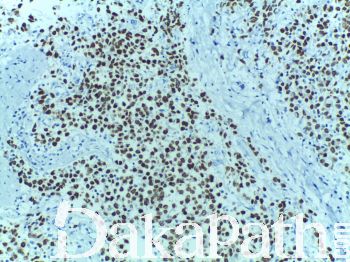

SALL4

锌指纹结构转录因子,负责调节胚胎干细胞的自我更新,是许多肿瘤中的关键基因,在胚胎发育过程中起重要作用,为干细胞标记及肿瘤胚胎蛋白,与 AFP 类似。SALL4 是精原细胞瘤和卵巢原始生殖细胞肿瘤敏感和特异的标记物,同时也是浸润性肝细胞癌类祖亚型的标志物,可作为肝细胞癌靶向治疗的潜在靶点。

信号定位: 胞核